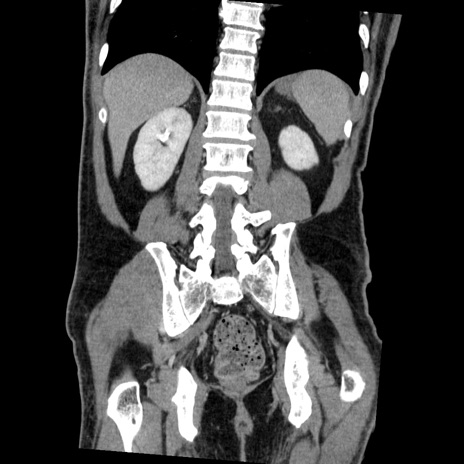

症例22(冠状断像)

【症例】50歳代男性

【主訴】腹痛

【現病歴】AVMからの被殻出血のため回復期リハ病棟入院中。 本日午後3時頃急に下腹部痛が出現した。

【既往歴】AVM、被殻出血、虫垂炎、高血圧

【身体所見】意識晴明、左半身不全麻痺、会話の理解は良好、36.5°C、腹部:膨隆、全体に板状硬、下腹部正中に圧痛点あり、反跳痛-、筋性防御不明、右下腹部にope scar

【データ】WBC 9400、CRP 0.06